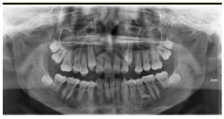

根尖片示:11自根中向远中弯曲约35°,属Ⅱ类弯曲牙,牙根发育至Nolla9期,21牙根发育至Nolla9期,腭侧见两颗正置锥形多生牙;12、22牙根发育至Nolla9期。

CBCT示:上颌恒牙胚萌出间隙不足,根据Moyers混合牙列分析法,牙弓现有长度为177.4 mm,牙弓应用长度为181.6 mm,拥挤度为4.2 mm。42缺失;11、21、22发育至Nolla9期;55、16、65、46冠部低密度影及牙本质中层,根管内未见高密度充填影,根尖周未见明显异常。53、63牙根吸收不足1/3,13、23发育至Nolla8期。

头颅侧位片示:下颌相对颅底位置靠前,趋向Ⅲ类错

,上下切牙舌腭向倾斜,骨龄CS1起始期。

患者母亲身高矮小、智力正常,下颌前突,曲面体层片示上下颌共缺失5颗恒牙(14、24、32、34、44),18、28、38、45、48阻生。